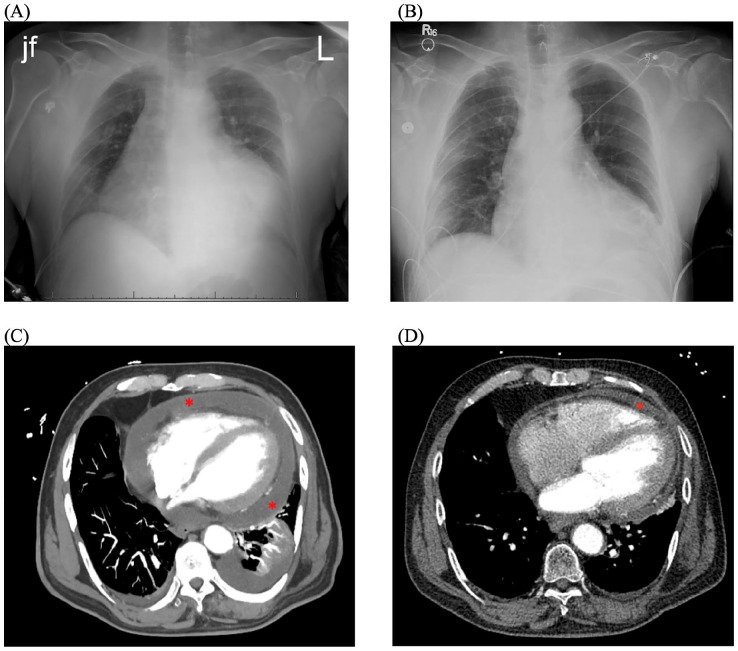

急性风湿热(ARF)是链球菌性咽炎的并发症,可伴有心脏、关节、皮肤和神经系统症状。心脏表现最常包括瓣膜功能障碍,但也可包括心肌炎或心包炎。尽管卫生保健方面的进步减少了链球菌性咽炎的流行,并随后减少了急性呼吸道感染,但仍可能发生个别病例和暴发。我们提出一例风湿性心包炎在一个60岁的白人男性谁最初提出的咽喉痛6天急诊科。最初的检查基本上是不起眼的,当时没有进行微生物检测。他被诊断为病毒性咽炎,在接受支持性治疗后出院。1周后复发胸膜性胸痛和呼吸困难。实验室检测显示炎症标志物、心脏酶标志物、抗溶血素O滴度和化脓性链球菌菌血症显著升高。进一步的评估显示心包炎,中度心包积液,无心包填塞,收缩功能降低,无瓣膜疾病。患者被诊断为风湿性心包炎。治疗方法包括心包引流、指南指导的药物治疗收缩期心力衰竭和心包炎,以及抗生素对ARF的一级治疗和二级预防。目前,患者的心脏功能已经恢复,他定期跟进他的医疗团队。虽然目前不太常见,但鼓励临床医生在出现咽部症状和随后的心脏表现,伴有或不伴有瓣膜功能障碍的患者的鉴别诊断中考虑链球菌性咽炎和ARF。一级和二级预防ARF对于维持该疾病的低发病率至关重要。

Acute rheumatic fever (ARF) is a complication of streptococcal pharyngitis that can present with cardiac, joint, skin, and neurological symptoms. Cardiac manifestations most often involve valvular dysfunction, but can also include myocarditis or pericarditis. Although advances in healthcare have reduced the prevalence of streptococcal pharyngitis, and subsequently ARF, individual cases and outbreaks can still occur. We present a case of rheumatic myopericarditis in a 60-year-old White male who initially presented to the emergency department with sore throat for 6 days. Initial workup was largely unremarkable, and no microbiological testing was performed at that time. He was diagnosed with presumed viral pharyngitis and discharged home with supportive care. He returned 1 week later with pleuritic mid-sternal chest pain and dyspnea. Laboratory tests were significant for elevated inflammatory markers, cardiac enzyme markers, anti-streptolysin O titers, and Streptococcus pyogenes bacteremia. Further evaluation revealed pericarditis, moderate pericardial effusion without tamponade, and reduced systolic function without valvular disease. The patient was diagnosed with rheumatic myopericarditis. Management included pericardial drainage, guideline-directed medical therapy for systolic heart failure and pericarditis, and primary treatment and secondary prevention of ARF with antibiotics. Currently, the patient's cardiac function has recovered, and he regularly follows up with his medical care team. Although less common in present times, clinicians are encouraged to consider streptococcal pharyngitis and ARF on the differential diagnosis for patients presenting with pharyngeal symptoms and subsequent cardiac manifestations, with or without valvular dysfunction. Primary and secondary prevention of ARF is paramount to maintaining the low incidence of this disease.